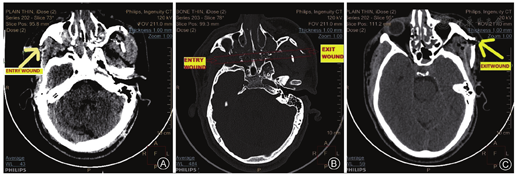

On radiological investigations, non-contrast CT scan of head revealed fractures in the posterolateral wall of the right orbit near the entry wound, medial wall of the right maxillary sinus, bilateral pterygoid plates, ethmoid air cells, vomer, medial as well as lateral wall of the left maxillary sinus and left zygoma, which were corresponding to exit wound of a gunshot injury (Fig. 3). Surprisingly, there was no damage to duramater and underlying brain tissue. All other radiological and blood investigations were within normal limits.